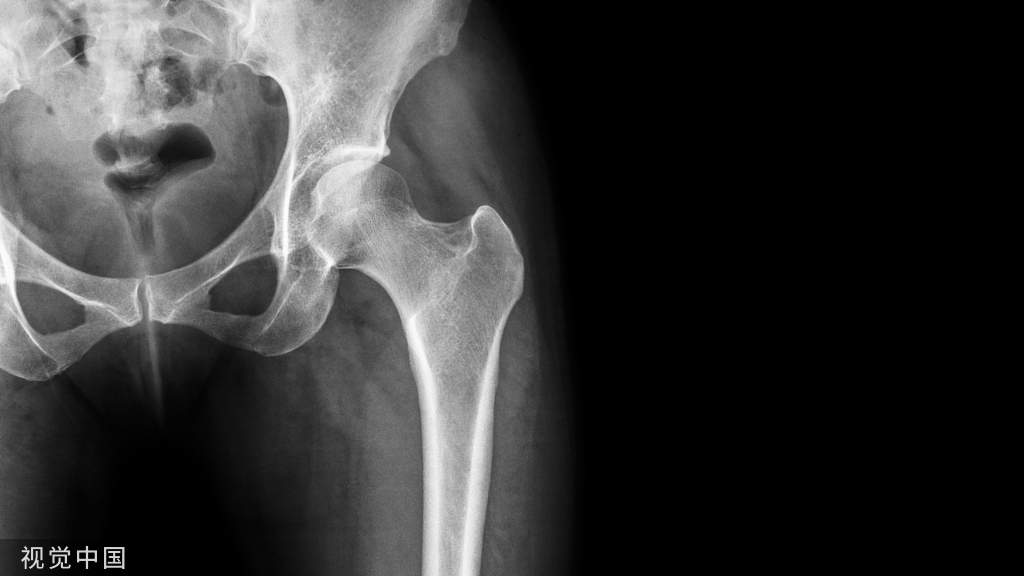

静脉血栓栓塞症(VTE)是骨科大手术围手术期的常见并发症,也是患者围手术期死亡及医院内非预期死亡的重要因素之一。

(3)高危因素:任何引起静脉损伤,静脉血流停滞及血液高凝状态的原因,其中骨科大手术是静脉血栓栓塞症的极高危因素。